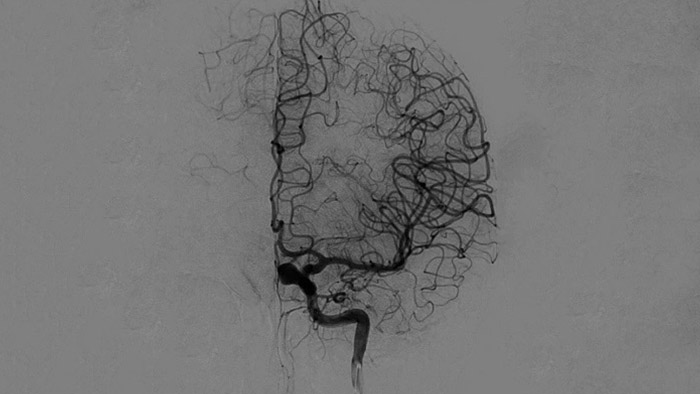

DSA Visualisierung

Hochwertige DSA-Visualisierungen ermöglichen es Ihnen, zu beurteilen, ob das Gerinnsel vollständig entfernt wurde und ob sich Teile davon distal in das Gehirn verteilt haben. Sie können die Wiederherstellung des Blutflusses zur Penumbra verifizieren und eine Überprüfung auf periprozedurale Blutungen vornehmen.